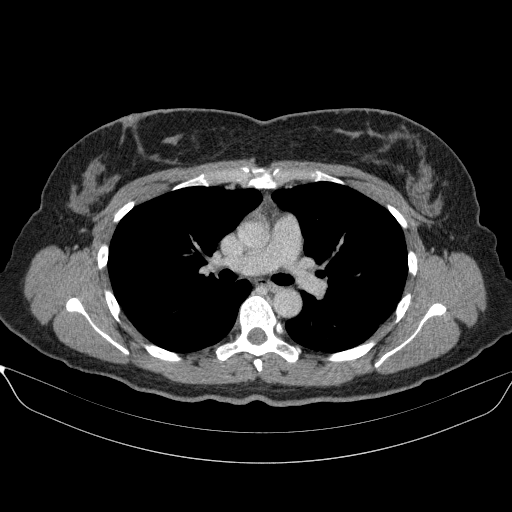

Image Grid

4Γ—3 grid: Rows show different image types (Original NATIVE, Reconstructed NATIVE, Original VENOUS, Generated VENOUS), Columns show windowing techniques (No Window, Lung Window, Mediastinum Window)

Original NATIVE CT scan (input)

No window - Raw intensity values

Reconstructed NATIVE CT scan (cycle consistency)

Original VENOUS CT scan

Generated VENOUS CT scan (A→B translation)